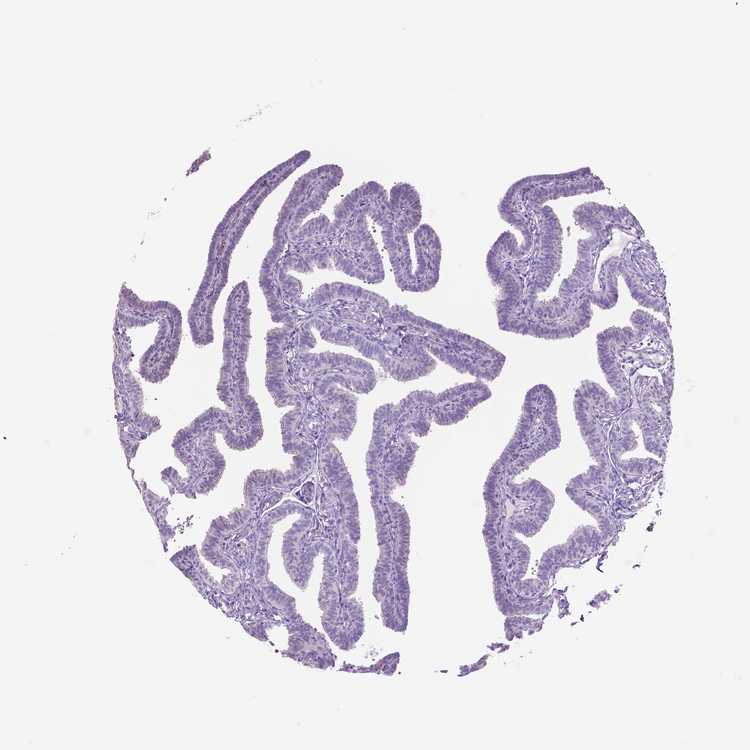

TISSUE PRIMARY DATA FALLOPIAN TUBE Show tissue menu

FALLOPIAN TUBE - Antibody stainingi

Antibody staining in the annotated cell types in the current human tissue is reported as not detected, low, medium, or high, based on conventional immunohistochemistry profiling in selected tissues. This score is based on the combination of the staining intensity and fraction of stained cells.

Each image is clickable and will lead to virtual microscopy that enables deeper exploration of all samples and also displays staining intensity scores, fraction scores and subcellular localization as well as patient and tissue information for each sample.

Antibody HPA001936

Glandular cells Not detected